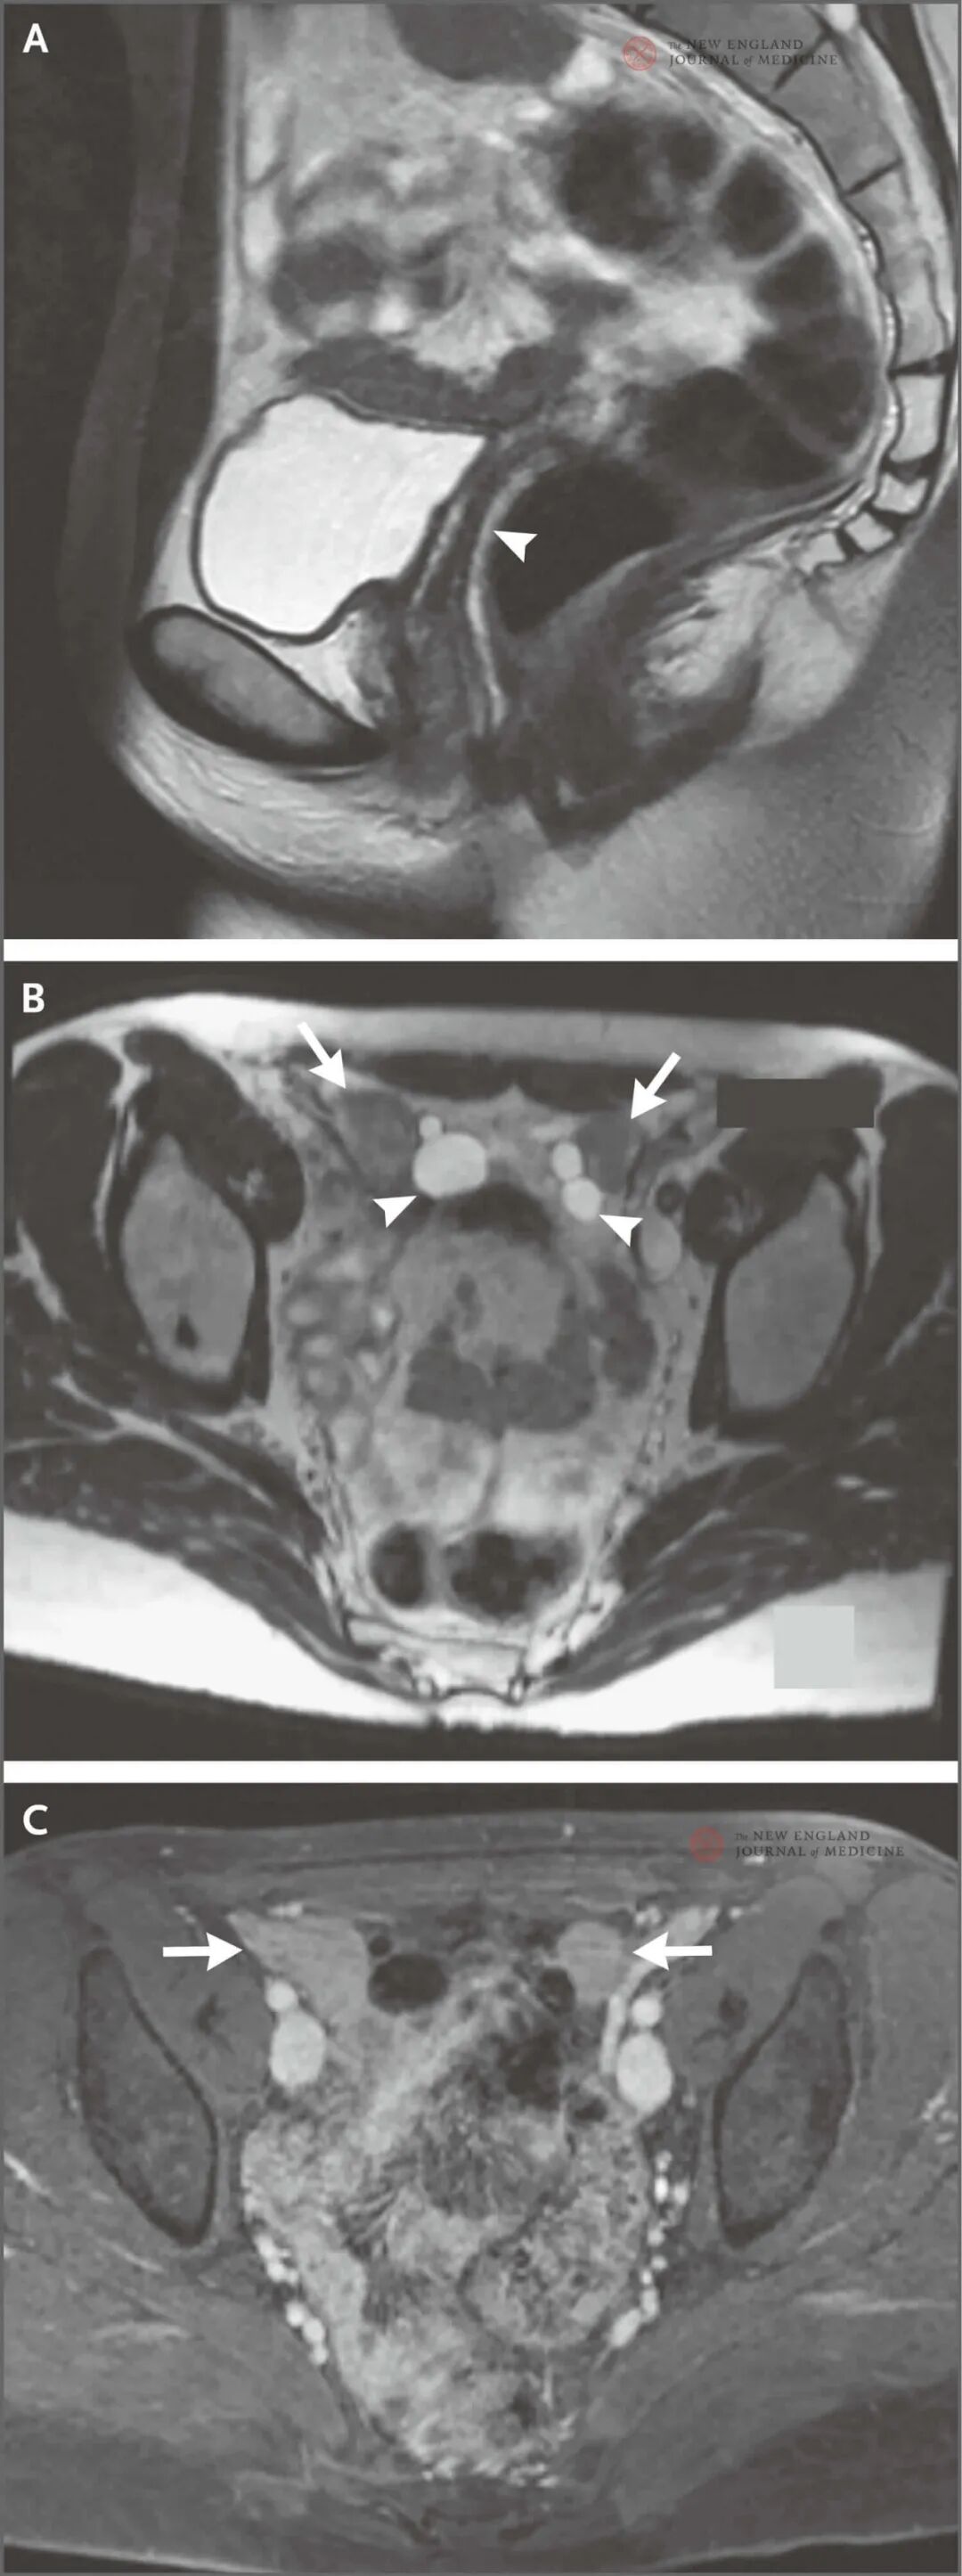

影像学检查结果盆腔MRI检查(图2)T2加权像(图A)显示阴道长度正常(箭头)。子宫和宫颈缺如。轴向T2加权像(图B)显示盆腔前部的性腺(箭形),以及性腺周围的多个囊肿(箭头)。未见明确的滤泡。给予造影剂后获得的轴向T1加权脂肪饱和图像(图C)显示两个性腺对称,均匀增强(箭形)。